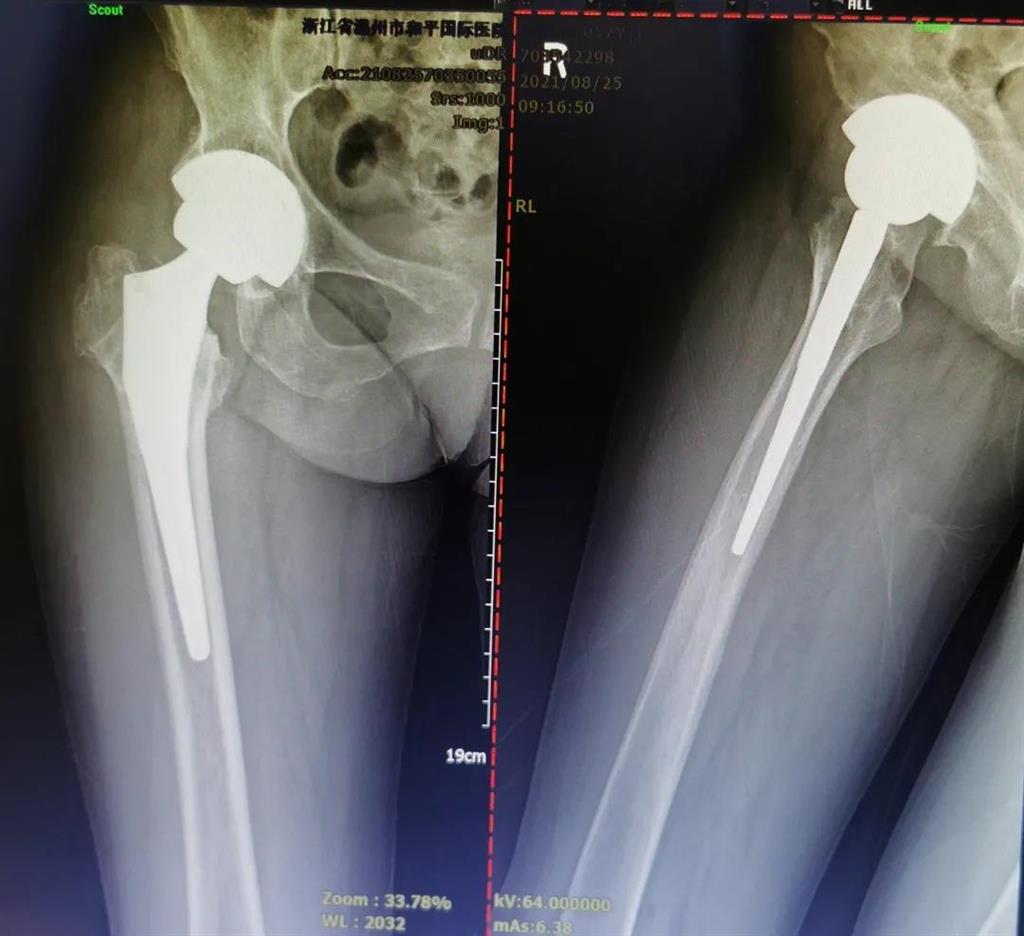

結(jié)合病癥表現(xiàn)及影像顯示,李女士被診斷為“右股骨頸骨折術(shù)后股骨頭壞死”,需要盡快做手術(shù)。

(△術(shù)前影像,右股骨頸骨折內(nèi)固定術(shù)后股骨頭壞死)

(△做完“右股骨頸全髖關(guān)節(jié)置換術(shù)”后的影像)